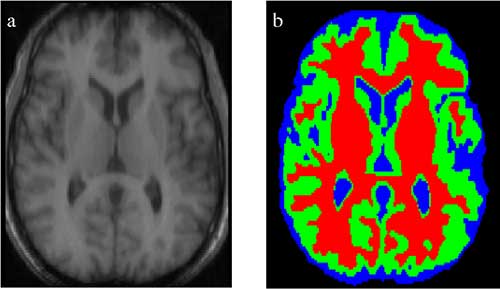

Medical Image Segmentation

Semantic Segmentation is used to identify salient elements in medical scans. It is especially useful to identify abnormalities such as tumors. The accuracy and low recall of algorithms are of high importance for these applications.

We can also automate less critical operations such as estimating the volume of organs from 3D semantically segmented scans.